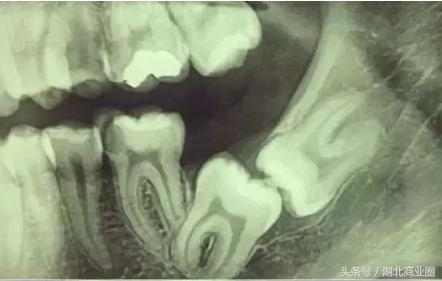

不拍CT永远不会知道,我的智齿还真爱秀恩爱啊!

终于见到了我的智齿,不拔简直不能忍。但是拔牙也不是小时候栓根绳子那么简单的一件事,医生嘱咐我另外约时间早上和中午之前来,今天太晚了,凝血后商场关门,医生也没有观察时间。